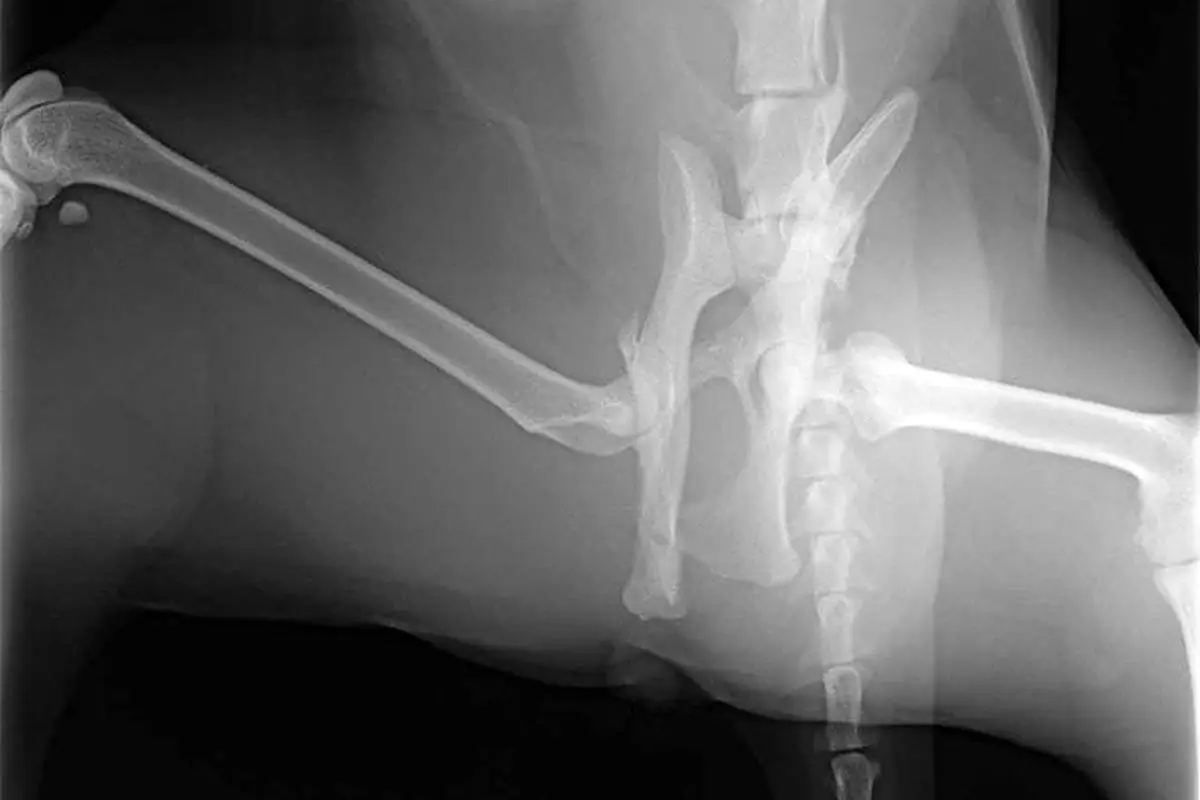

Veterinarijos gydytojas atidžiai studijuoja katę ir gauna savo istoriją. Fizinės apžiūros metu galite klausytis intervalo. Diagnozę galima patikrinti X -srautą.

Be to, norint patikrinti, ar nėra vidinės žalos, turite atlikti x -G krūtis.